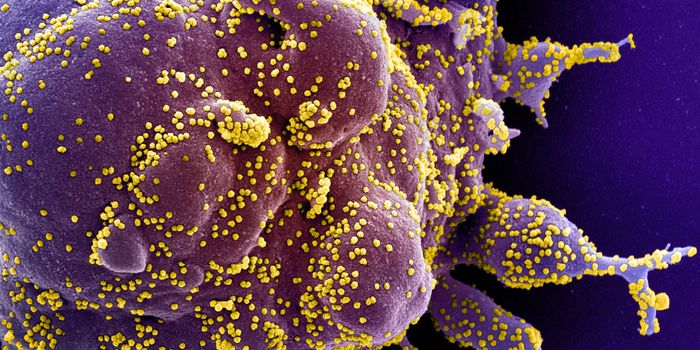

SEP 20, 2021Genetics & GenomicsHuman immunodeficiency virus (HIV) is a retrovirus, which is a type of virus that can write its genetic material into th ...